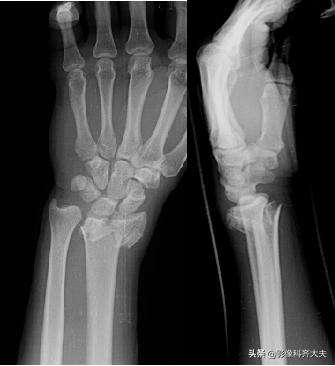

Colles骨折:伸展型桡骨远端骨折,在桡骨远端2-3cm以内的横行或粉碎骨折,远侧向桡或背侧移位,常合并尺骨茎突骨折。